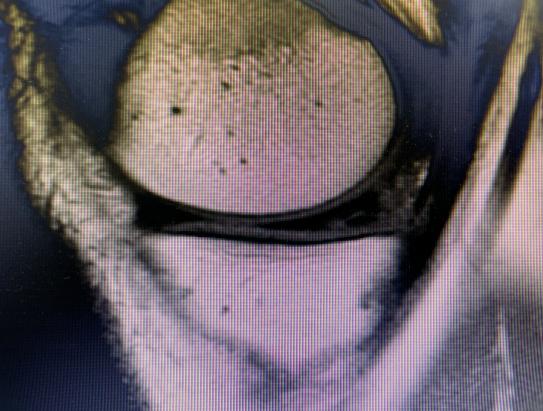

膝关节(双侧)平扫检查结果提示:(1)双膝关节轻度退变,内、外侧半月板后角Ⅱ °损伤。(2)左膝前交叉韧带轻度损伤。(3)双膝关节腔及髌上囊积液。

经PRP治疗1年后,患者因扭伤再次就诊,进行膝关节(双侧)平扫检查,结果提示:(1)双膝关节轻度骨质增生。(2)内、外侧半月板后角退变。(3)左膝前交叉韧带信号增高,炎症反应或损伤待除外。(4)双膝关节腔及关节周围软组织水肿。(5)双侧关节腔及髌上囊少量积液。通过检查结果,可以看出患者经PRP治疗后内、外侧半月板后角损伤有明显好转,从Ⅱ°损伤降至Ⅰ°损伤,且双膝关节腔及髌上囊积液减少。